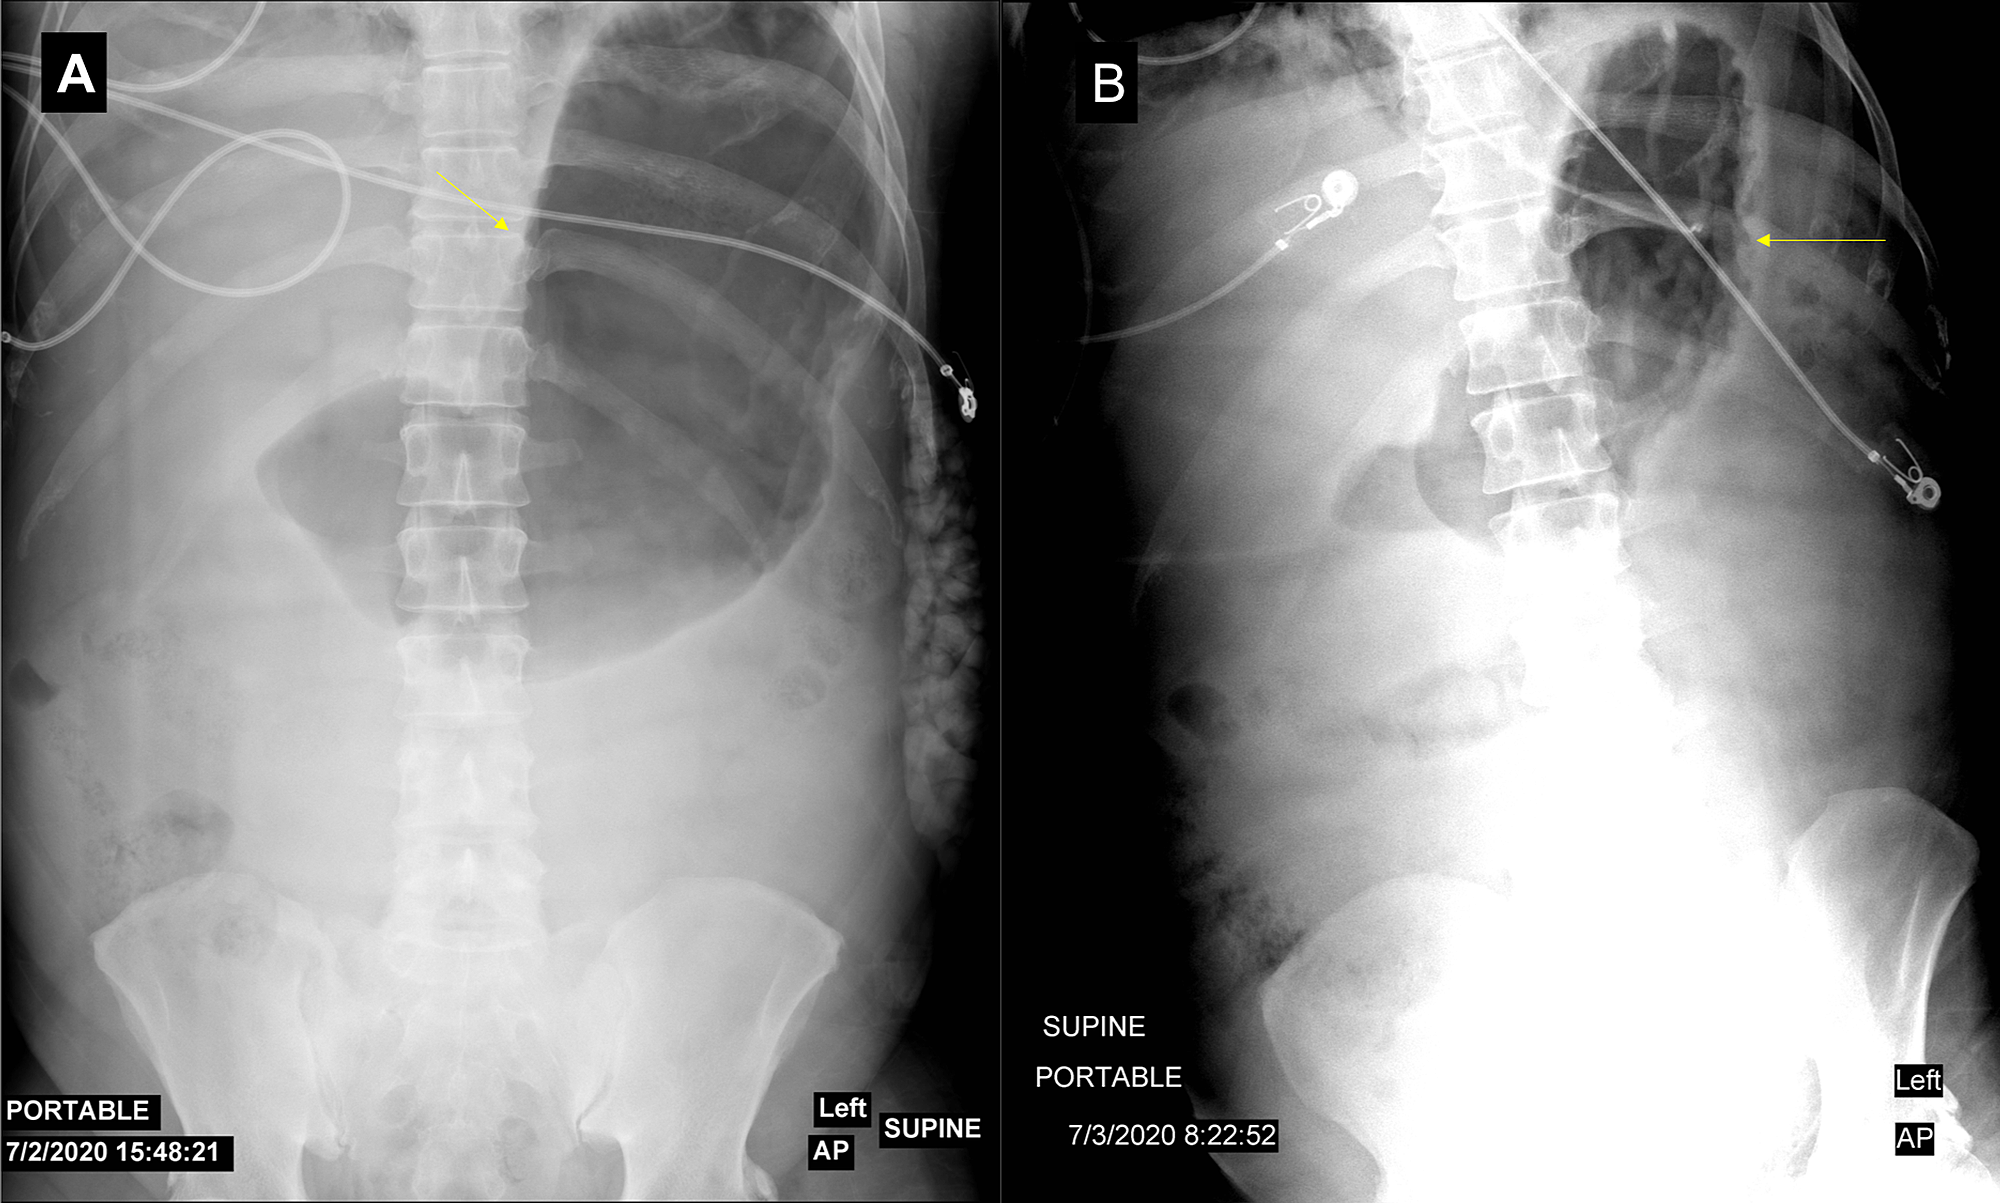

An ultrasound of the gallbladder was done upon admission, which showed no evidence of biliary stones. The patient was kept nil per os (NPO) and was started on 250 mL/h of lactated Ringer’s solution. The pain was controlled with intravenous hydromorphone, and the patient was transferred to the ICU for close monitoring. After six hours, the abdominal pain worsened, and the patient developed abdominal distension and increased bladder pressure (34 mmHg). A kidney, ureter, and bladder (KUB) X-ray revealed significant gastric distention (Figure 2A). Given the suspicion of abdominal compartment syndrome (ACS), the patient was placed in a supine position and received muscle relaxants. A nasogastric tube (NGT) was inserted and the surgical team was consulted. The patient was managed with these conservative measures, and a follow-up KUB (Figure 2B), bladder pressure, and abdominal examination showed significant abdominal decompression.

As ileus and gastroparesis are often present in acute pancreatitis, reducing the intraluminal volume of the gastrointestinal tract is a logical first step. In the case of gastric dilatation, nasogastric decompression can easily be done and may have a significant impact on IAP [20]. Our case, with severe IAH, showed an excellent response to the insertion of NGT and the use of muscle relaxants.